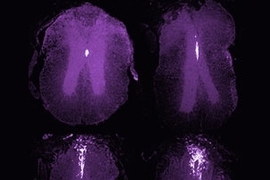

Engineering Scaffold-Mediated Neural Cell Therapy for Spinal Cord Injury Treatment (ScaNCellS), the second research project, gathers an interdisciplinary group of engineers, cell biologists, and clinician scientists from SMART, Nanyang Technological University (NTU), NUS, IMCB A*STAR, A*STAR, French National Centre for Scientific Research (CNRS), the University of Cambridge, and MIT. The team will seek to design a combined scaffold and neural cell implantation therapy for spinal cord injury treatment that is safe, efficacious, and reproducible, paving the way forward for similar neural cell therapies for other neurological disorders. The project, an intersection of engineering and health, will achieve its goals through an enhanced biological understanding of the regeneration process of nerve tissue and optimized engineering methods to prepare cells and biomaterials for treatment.